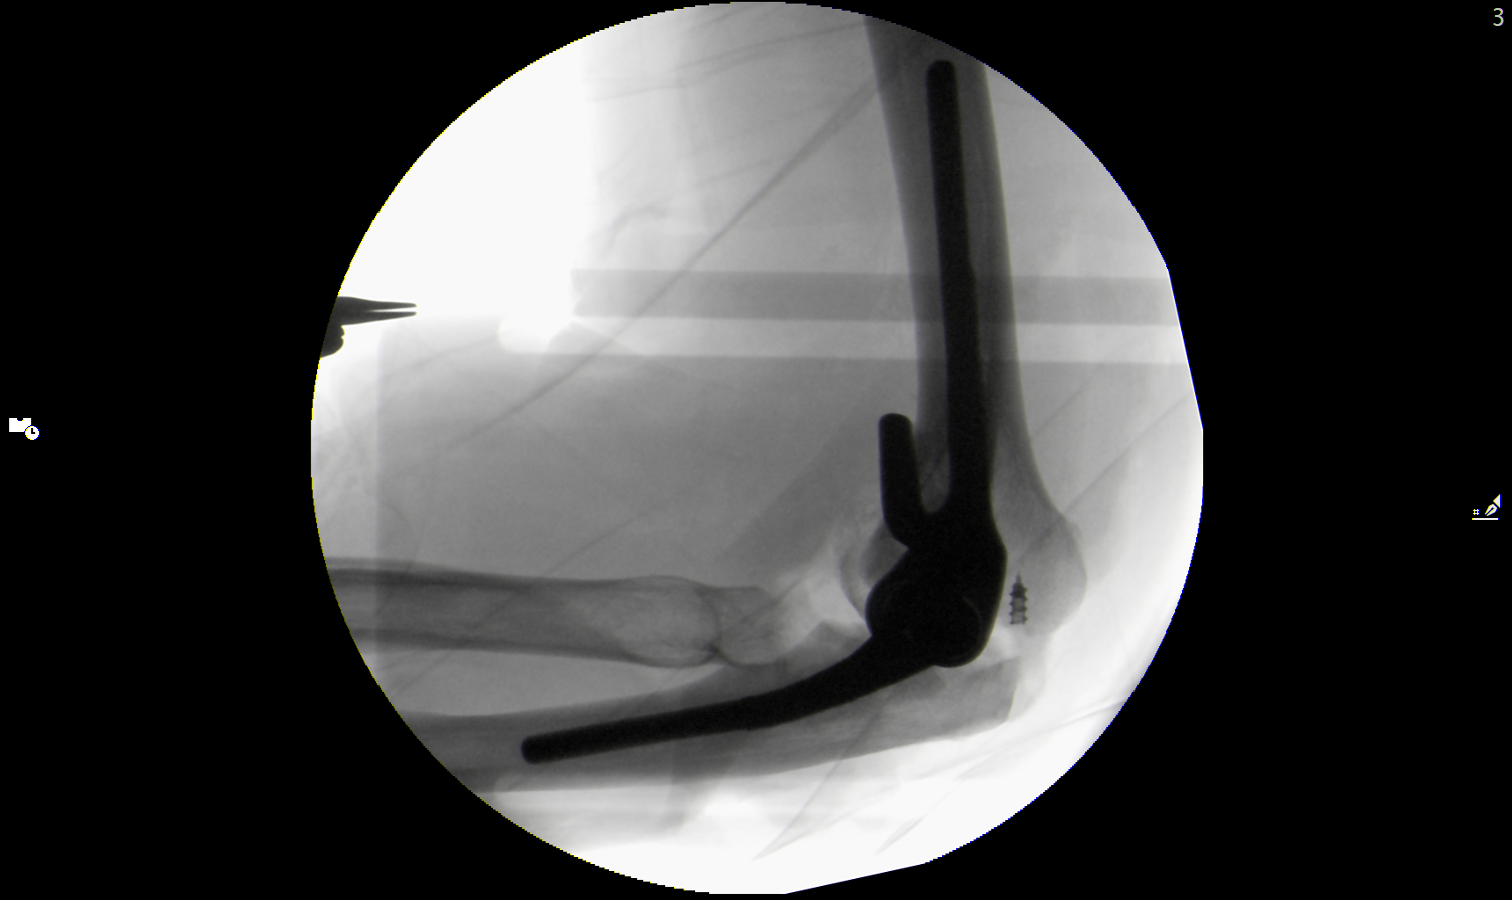

Ich habe einem Mann mit einer posttraumatischen Behinderung, der seit vielen Jahren unter anhaltenden Ellenbogenschmerzen litt, ein künstliches Ellenbogengelenk operiert. Es handelte sich um eine sehr anspruchsvolle, mehrstündige Operation, da auch die Beweglichkeit des Gelenks wiederhergestellt werden musste. Damit das künstliche Ellenbogengelenk (Endoprothese) des Patienten möglichst lange hält, nähe ich in solchen Fällen auch beide Seitenbänder wieder an ihren ursprünglichen Platz, was kein üblicher Teil der Operation ist, aber die Belastung der Endoprothese wird damit verringert.